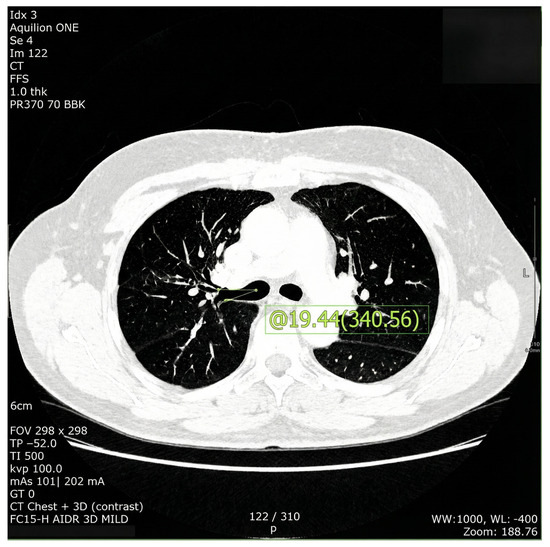

Background/Objectives: Accurate knowledge of tracheobronchial anatomy is essential for safe airway management, particularly during one-lung ventilation using double-lumen tubes (DLTs). However, population-specific morphometric data in Asian adults remain limited. We aimed to establish a comprehensive morphometric profile of the tracheobronchial tree in Korean adults using 2D and 3D computed tomography (CT), and evaluate the clinical implications for DLT sizing and right upper lobe (RUL) alignment. Methods: This retrospective observational study included 398 adults who underwent preoperative chest CT. Measurements included tracheal dimensions, bronchial lengths, bronchial diameters, and anteroposterior angle of the RUL orifice. Height tertiles and sex-stratified linear regression analyses were performed to evaluate height–bronchial diameter relationships. Results: Bronchial dimensions were larger in men; however, height was more closely related to bronchial diameter in women. In women, each 1 cm increase in height corresponded to a 0.071 mm increase in left and a 0.077 mm increase in right bronchial transverse diameter (p < 0.001 for both). The RUL orifice showed posterior deviation of 15.5 ± 12.2° in men and 9.9 ± 11.4° in women, with height and weight being independent but weak predictors (R2 = 0.05). Bronchial diameter measurements showed consistent differences between 2D and 3D CT, with 2D images generally overestimating transverse diameters. Conclusions: The present analysis provides population-specific reference values for Korean adults. Our findings support the use of 2D CT as a practical tool for estimating bronchial dimensions and guiding DLT selection, and may serve as foundation for future airway devices tailored to Asian populations. Full article